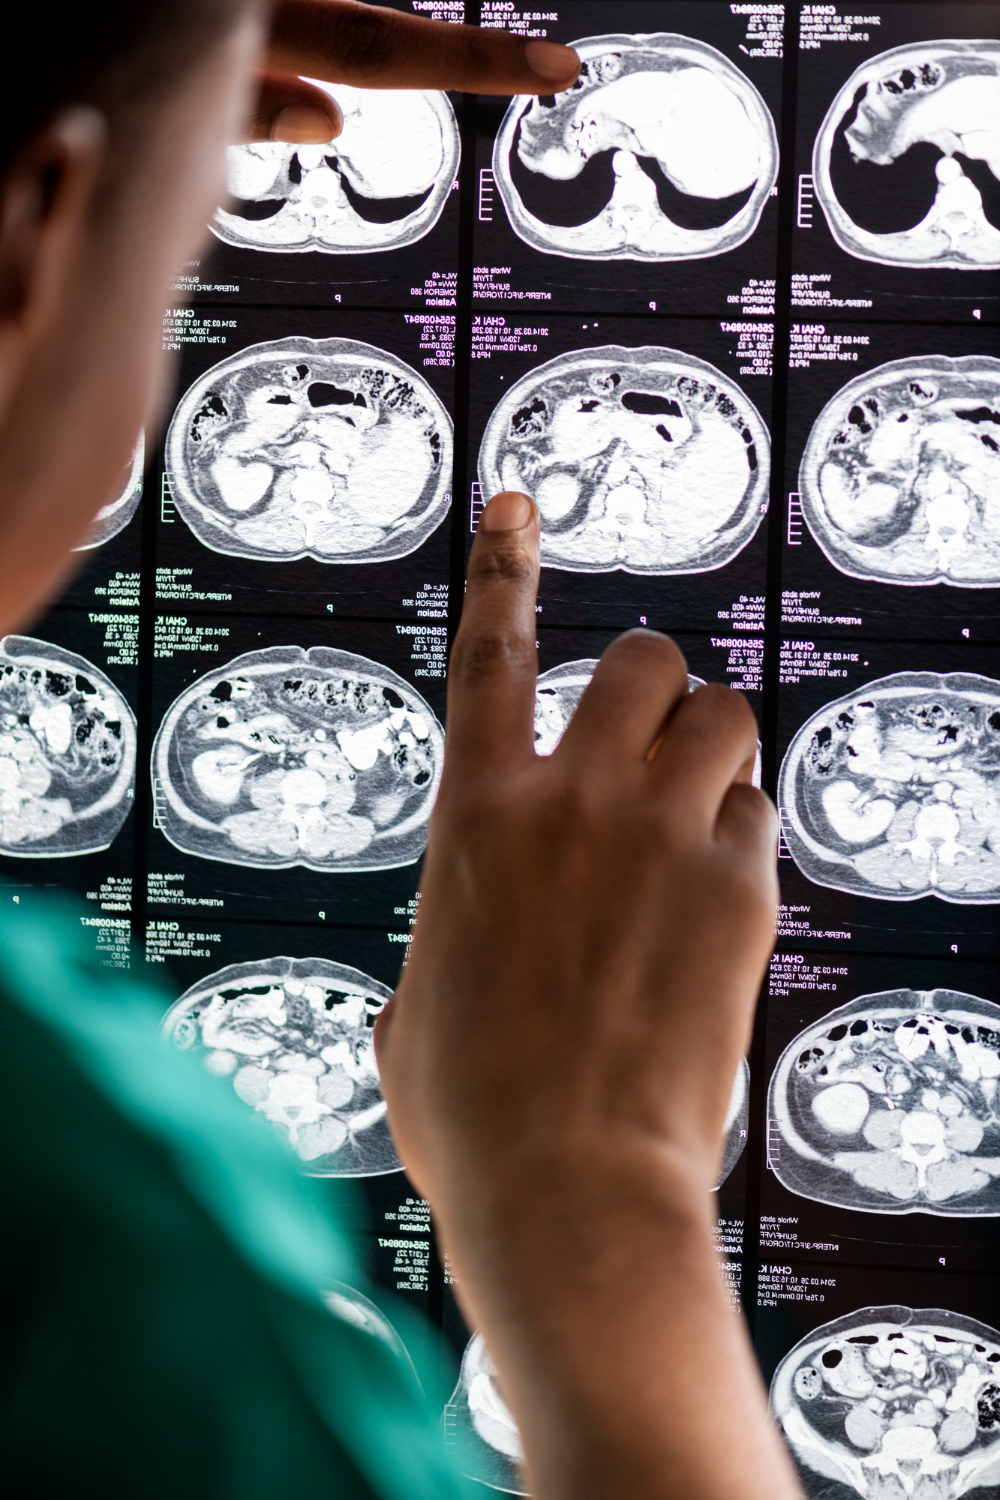

Tumores cerebrais

Os tumores cerebrais são alterações que podem comprometer funções importantes do cérebro, como memória, fala, visão e coordenação motora. Cada caso exige avaliação cuidadosa e abordagem individualizada. Na Clínica N3, realizamos diagnóstico especializado e oferecemos tratamento personalizado, com acompanhamento contínuo e equipe experiente em neurologia e neurocirurgia. Nosso compromisso é garantir segurança, eficácia e qualidade de vida para o paciente e sua família.

Segurança e experiência no cuidado de tumores neurológicos

A Clínica N3 é referência no diagnóstico e tratamento de tumores cerebrais, da medula espinhal e de nervos periféricos, oferecendo acompanhamento completo e personalizado para cada paciente. Com uma equipe de profissionais altamente qualificados em neurologia e neurocirurgia, aliamos experiência, tecnologia avançada e cuidado humanizado em todas as etapas do tratamento. Nosso compromisso é proporcionar segurança, eficácia e qualidade de vida, consolidando a Clínica N3 como um centro de excelência em Londrina e região.